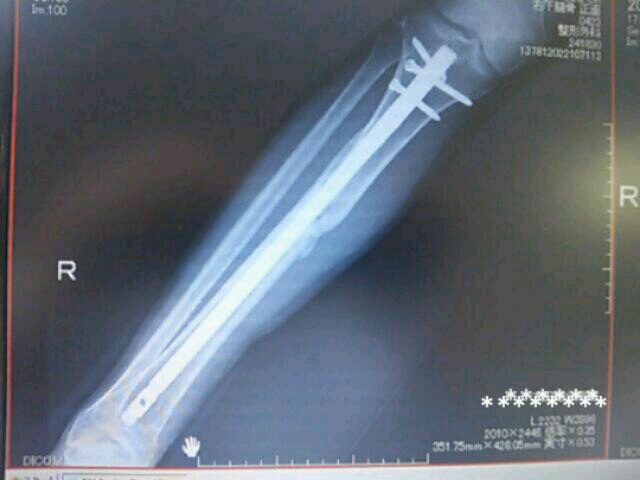

キュンチャー髄内釘!

髄内釘さすがご存知!!